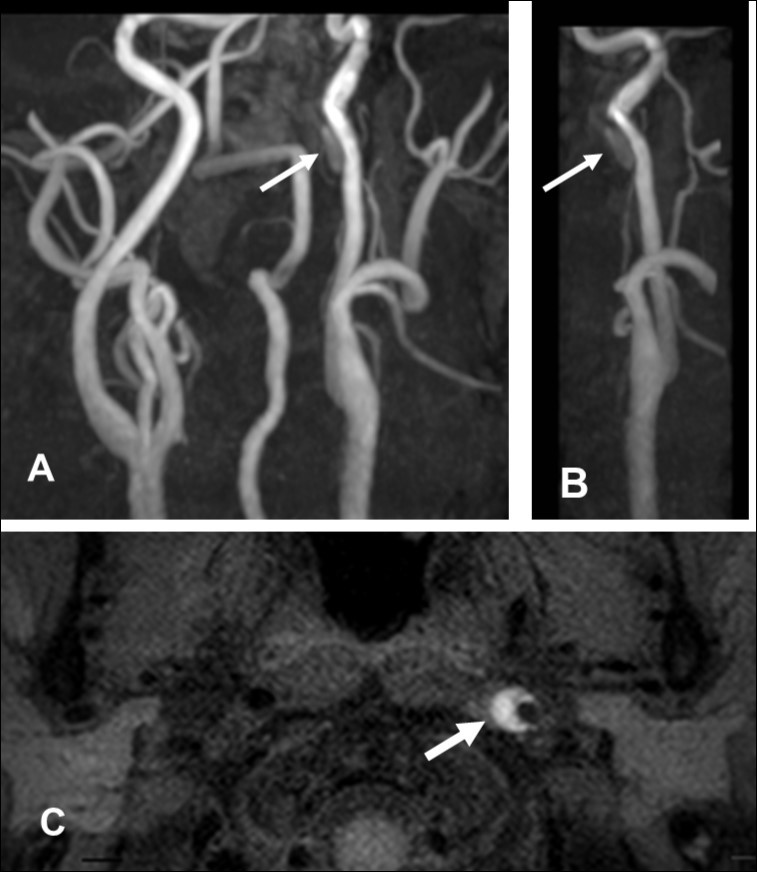

Figure 1.First hospitalization. A. Maximum intensity projection ( MIP )image of arteries in the cervical segment. B. Magnetic resonance angiography of the left carotid artery. C. T1 VISTA sequence. Note the flow void reflective of the narrowed lumen next to intramural hematoma (hyperintense crescent)

First hospitalization. A. Maximum intensity projection ( MIP )image of arteries in the cervical segment. B. Magnetic resonance angiography of the left carotid artery. C. T1 VISTA sequence. Note the flow void reflective of the narrowed lumen next to intramural hematoma (hyperintense crescent)

This 43-year-old Japanese male presented with right hand dysesthesia. He has not recognized his neck pain and Horner’s syndrome( oculosympathetic palsy). Magnetic resonance imaging(MRI) performed on a 3T TX scanner (Philips Achieva, The Netherlands) demonstrated dissection of the left cervical carotid artery (CCA; Figure 1A,1B ); no ischemic area was detected in the left cerebral brain. Axial section views of the CCA segment revealed a typical crescent hematoma; a bright, hyper-intense circle representing the narrowed arterial lumen was visualized. A T1-volumetric isotropic turbo spin echo acquisition (VISTA) sequence resulted in the diagnosis of dissection of the CS-ICA (Figure 1C). He had no conventional stroke risk factors such as hypertension, diabetes, hyperlipidemia, a history of cardiac valvular disease, arterial fibrillation, or features of inherited connective tissue disorder. Also absent was a history of arterial trauma and we were unable to identify any etiological factor(s). One week later he developed Gerstman symptoms; border zone ischemia was observed in the left cerebrum (Figure 2-Ic). He was admitted and the administration of antiplatelet agents was started. The left middle cerebral artery (MCA) was supplied via antegrade circulation (Figure 2-Ib) and an increase in the flow-void intensity was noted (compare Figure 1C with Figure 2-Ia). MRI studies acquired one week later revealed spreading of the ischemic area to beyond the watershed zone between the left anterior cerebral artery (ACA) and the MCA, and the MCA and the posterior cerebral artery (PCA) (Figure 2-IIc). The area of dissection had spread from the ICA bifurcation to the top of the ICA. The blood supply to the left MCA territory derived from the circle of Willis (Figure 2-IIb). The flow-void intensity had increased further (compare Figure 2-Ia with Figure 2-IIa). Two weeks after his admission he suddenly experienced complete right-sided hemiparesis with motor aphasia. MRI performed within 45 min demonstrated diffuse ischemia in the left MCA territory (Figure 2-IIIc), the left A1 segment could not be visualized. The left MCA and its A1 segment were completely occluded (Figure 2- IIIb). The flow-void intensity indicated complete occlusion of the true lumen (Figure 2-IIIa). He underwent emergency left superficial temporal artery (STA)-MCA bypass surgery within 6 hours; double anastomosis was successful. External decompression was performed to prevent neurological deterioration due to severe brain swelling. An intensive rehabilitation has been continued for him after operation. His functional independence measure (FIM) score recorded over the course of 4 months showed remarkable improvement ( Figure 3) as did the standard language test for aphasia.